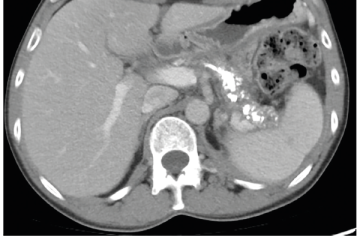

Několik studií se zabývalo AI asistovanou CT detekcí karcinomu pankreatu s AUC 0,79–0,99 %,6–8 tedy přesností porovnatelnou s přesností práce zkušeného radiologa. Stran časné detekce proběhla studie posuzující přesnost AI modelu v detekci karcinomu pankreatu v období 3–36 měsíců před prvními projevy onemocnění. Zařazeno bylo 155 pacientů s karcinomem pankreatu a 265 zdravých kontrol. AI model zde dosáhl AUC 0,98, což výrazně předčilo radiology, kteří při popisování stejných případů dosáhli AUC 0,66.9 Studie využívající DL model pro rozlišení zdravé slinivky od nálezu pankreatických neoplazií, tedy karcinomu pankreatu, intraduktální papilární mucinózní neoplazie (IPMN), serózních a mucinózních cystických neoplazií a solidní pseudopapilární neoplazie, byla prezentována s AUC 0,91, tedy opět odpovídající přesnosti popisu radiologa.10 Pro další vývoj a možné klinické využití bude potřeba přístupu k rozsáhlému archivu CT snímků karcinomu pankreatu, aby se ML modely mohly zdokonalovat. Další studie se věnovaly AI asistované diferenciální diagnostice. Ta bývá u lézí pankreatu velmi obtížná a pokrok v této problematice je tak velmi přínosný. Mezi nejzajímavější patří studie zabývající se rozlišením serózních a mucinózních cystadenomů s AUC 0,932.11 Další studie zkoumala úspěšnost rozlišení karcinomu pankreatu od zbytnění pankreatu při určitých formách chronické pankreatitidy (MFP – mass forming pancreatitis) s AUC 0,866.12 V další studii byla AI využita k rozlišení fokální autoimunitní pankreatitidy od karcinomu pankreatu s AUC 0,97.13 V rámci MR proběhlo několik studií, které se zaměřily na AI asistované zachycení a klasifikaci pankreatického karcinomu či IPMN. Studie klasifikující IPMN pomocí konvoluční neuronové sítě (CNN – convolutional neural network) byla schopna rozlišit dysplazii vysokého stupně od přítomnosti karcinomu se senzitivitou 76 %, specificitou 78 % a AUC 0,78.14 Další studie porovnávala AI modely CT a MR v predikci maligního IPMN. Výsledky ukázaly, že MR model s AUC 0,94 byl přesnější než CT model s AUC 0,864.15 S využitím PET/CT byl prozkoumán AI model rozlišující od sebe akutní pankreatitidu a karcinom pankreatu s AUC 0,9668.16 Výsledky AI v oblastech zobrazovacích metod jsou tak slibné. Dosahují minimálně přesnosti srovnatelné s radiologem a zejména v problematice časných karcinomů pankreatu člověka svojí přesností převyšují (obr. 1–5).